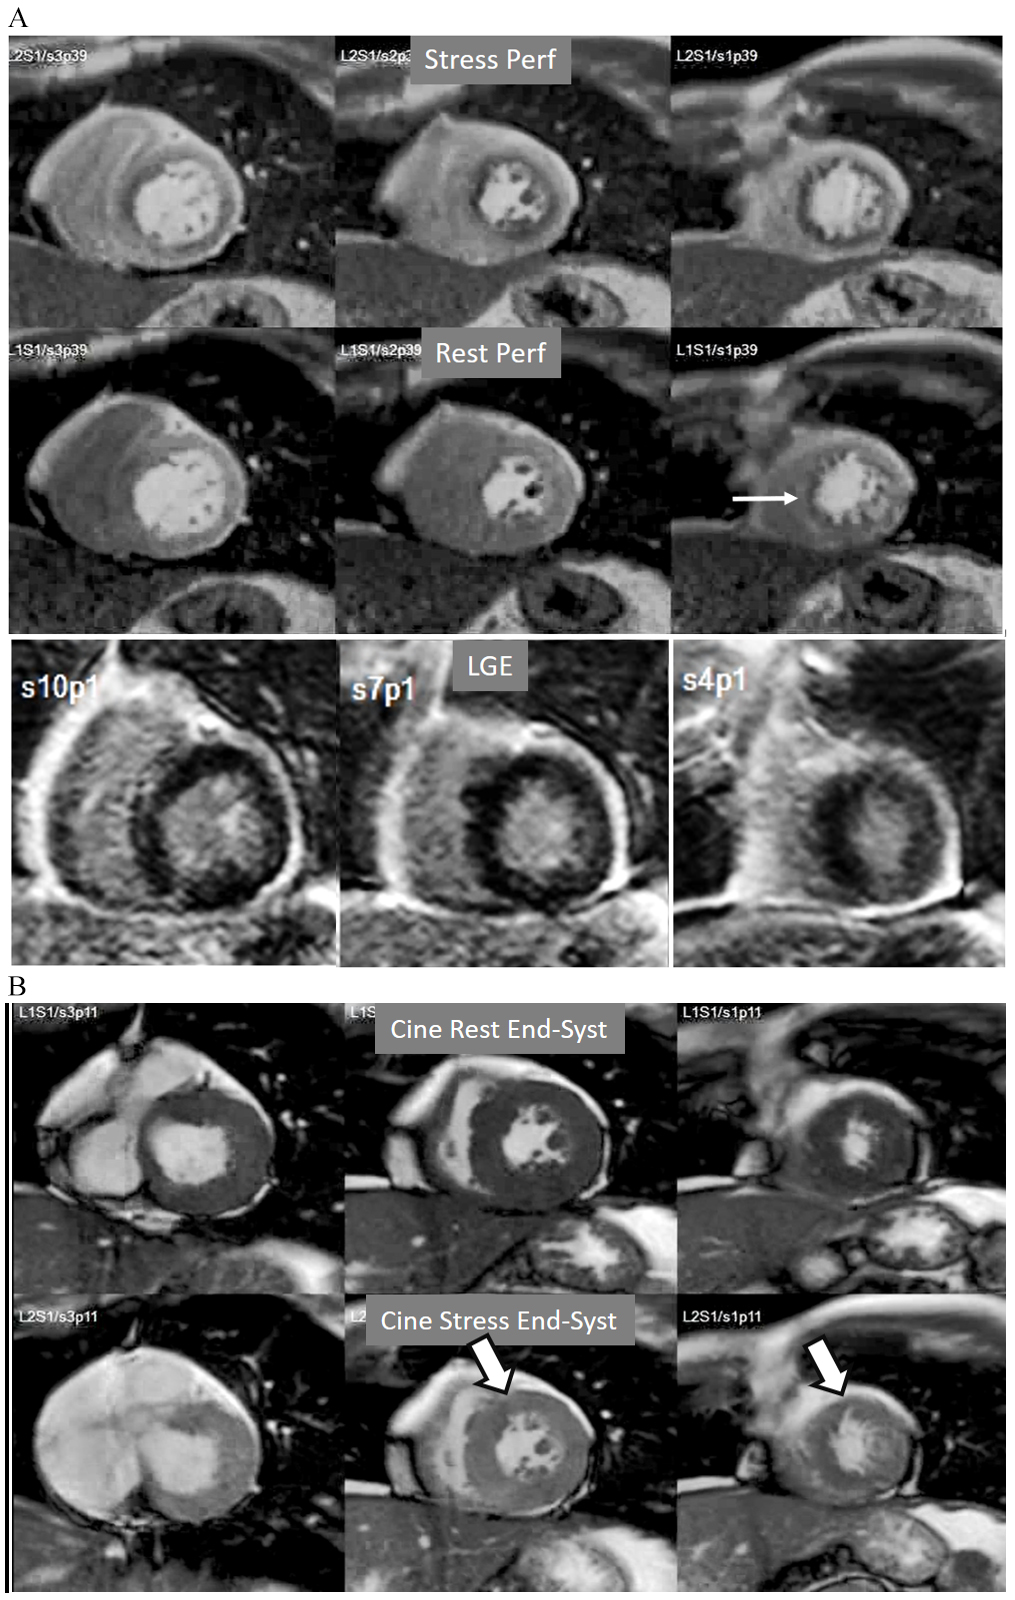

A not infrequent finding is a diffuse, annular, transient, subendocardial defect not present at rest (Fig. 9), which, in the absence of any recognizable obstructive lesion in an epicardial coronary artery, has been deemed to correspond to diffuse microvascular dysfunction (MVD) [41, 42]. CMR perfusion is sensitive to both the downstream effects of discrete epicardial stenoses and those due to disturbances of coronary microcirculation, and subendocardial hypoperfusion is on the pathophysiological basis of each one. For this reason, theoretically, a global, inducible subendocardial defect, could also be due to multivessel epicardial disease with balanced ischemia. In practice, however, this latter instance presents with extensive but heterogenous defects in terms of intensity, persistence and transmurality and, not rarely, also with perfusion defects at rest (Fig. 10A). Importantly, an accompanying induced contractile disfunction may be found in particularly impaired regions (Fig. 10B), a finding which is never seen in MVD.

Fig. 10.Multi-vessel perfusion defect. (A) Global stress hypoperfusion in a patient with multivessel CAD. Observe the non-uniformity of the defect, with different degrees of intensity and transmurality and, also, with the presence of a defect at rest (arrow), in the absence of LGE. (B) End-systolic frames from cine studies at the same level of the perfusion slices showing inducible antero-septal hypokinesia during stress (arrows).